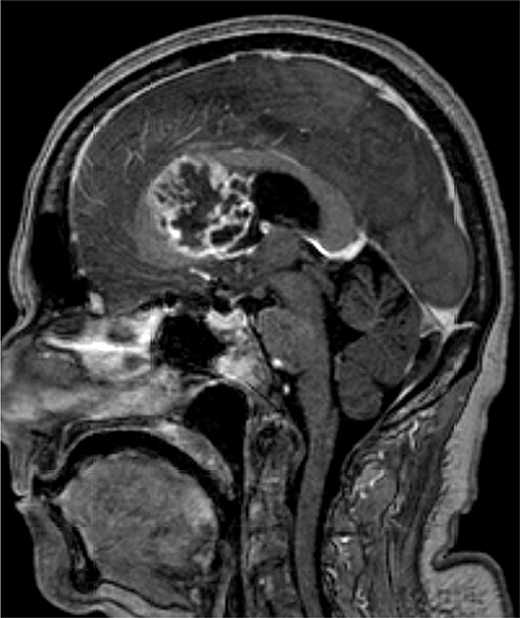

Bij neurologisch onderzoek reageert ze traag, is haar concentratievermogen verminderd en heeft ze een breed-basisch looppatroon. Een MRI-scan laat een groot ruimte-innemend proces rechts frontaal zien [figuur 1–3]. Na partiële turmorresectie wijst histologisch onderzoek uit dat het om een glioblastoom gaat.

Figuur 2 | Sagitale coupe van de MRI-hersenen; zie de omschrijving van figuur 1.

Een glioblastoom bestaat meestal uit een enkele massa die zich supratentorieel bevindt. 5 Bij beeldvormend MRI-onderzoek wordt de tumor veel beschreven als een ‘door een ring omgeven’ laesie, zoals ook in deze casus [figuur 1]. Door deze ringvorm wordt een glioblastoom soms foutief gediagnosticeerd als een abces. 9 Hooggradige gliomen hebben abnormale vaten die veel ‘lekken’ doordat de bloed-hersenbarrière abnormaal permeabel is, waardoor er op MRI-beelden meestal contrastaankleuring te zien is. Een glioblastoom kan doorgroeien naar aanliggende hersenkwabben of via de liquor. Hij metastaseert echter zelden buiten het zenuwstelsel. 5